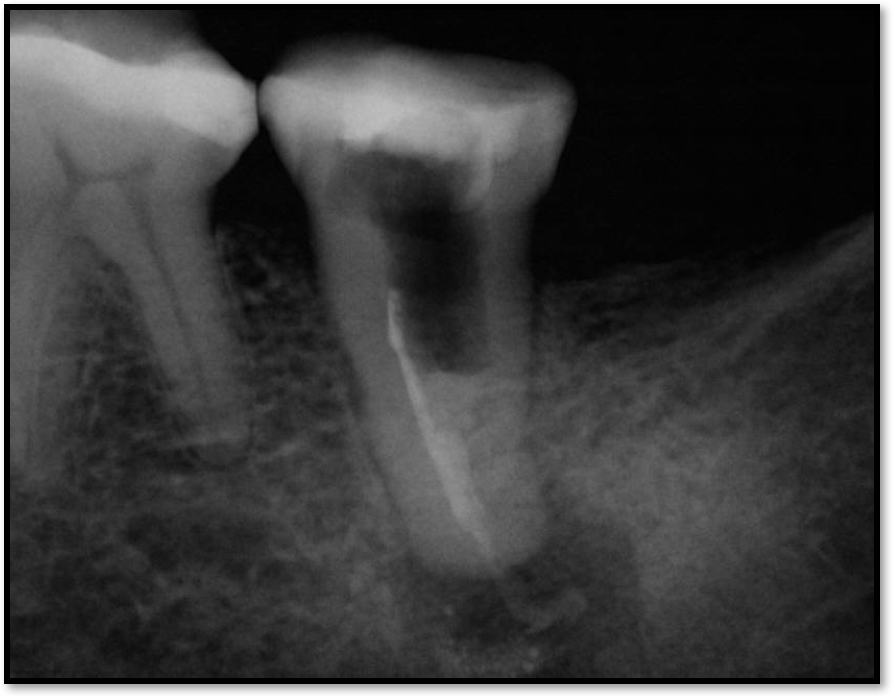

Fig 12. The post was too long.

Figure 12

Figure 12 shows an example of a post that was too long. Although it was a pleasant-looking threaded post, there was about a millimeter of gutta-percha, where ideally 4 to 5 mm of gutta-percha would be used.8 This was also an iatrogenic problem where the referring dentist put a post directly into the furcation. This type of problem can be fixed by removal and repairing with MTA. However, because there was not much tooth structure, the tooth became far more compromised.